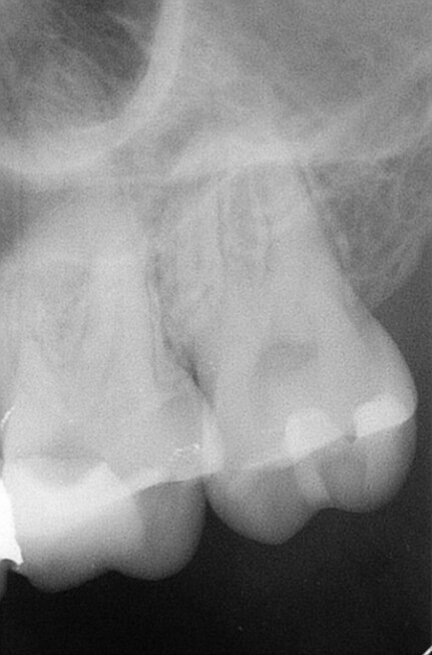

Copious irrigation with 5% sodium hypochlorite was performed during the shaping and cleaning procedures. Copious irrigation with 5% sodium hypochlorite was performed during the shaping and cleaning procedures. An ultra sonic tip (Endo Chuck, EMS) and sonic powered irrigation tip (EDDY, VDW) were used to activate the irrigants. At the end, the canals were irrigated with 17% EDTA, and this solution was kept in the canals for 2 minutes. The canals were dried with paper points. An epoxy-amine root canal sealer and a master gutta-percha cone were placed in the canals and the canals were obturated using the continuous wave obturation technique. Glass ionomer cement was used as a temporary filling material (Fig. 3). The patient was referred for final restoration to his general dental practitioner.